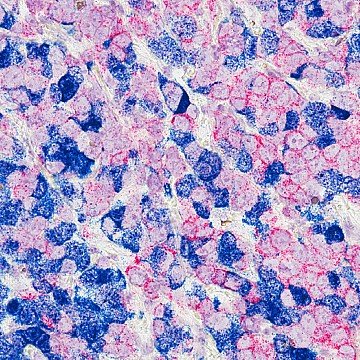

Científicos desarrollaron una nueva terapia celular para el cáncer de mama triple negativo, uno de los más agresivos y difíciles de tratar. En este estudio usaron células inmunitarias creadas a partir de sangre del cordón umbilical y las modificaron para reconocer y atacar las células tumorales.

El cáncer de mama triple negativo, no responde bien a los tratamientos más comunes, como las terapias hormonales o dirigidas, y suele tener pocas opciones efectivas cuando se vuelve resistente o se extiende a otras partes del cuerpo. Por ello los científicos están probando una terapia innovadora que usa células del sistema inmunitario modificadas en el laboratorio para reconocer y destruir las células del tumor.

Los investigadores crearon un tipo especial de células inmunitarias “entrenadas” llamadas CAR-NKT.

• NKT son células que funcionan como una mezcla entre dos tipos de defensores del cuerpo: las células T (que reconocen amenazas específicas) y las células NK (que atacan rápidamente lo que parece peligroso).

• Estas células fueron fabricadas a partir de células madre de la sangre del cordón umbilical. Esto permite crear un tratamiento “listo para usar”, que no necesita personalizarse para cada persona, lo que podría hacerlo más rápido y más barato.

• A las células NKT les añadieron un “sensor” especial (un receptor CAR) para que puedan reconocer una proteína llamada mesotelina, que está presente en muchas células de este tipo de cáncer pero no en las sanas.

• También las programaron para producir una sustancia llamada IL-15, que les ayuda a sobrevivir y mantenerse activas por más tiempo.

Resultados del estudio con células de cáncer en el laboratorio y en ratones con tumores humanos:

1. Las células CAR-NKT atacaron eficazmente las células del cáncer de mama triple negativo.

2. No solo destruyeron las células cancerosas directamente, sino que también eliminaron otras células “protectores del tumor” que suelen bloquear la respuesta del sistema inmunitario.

3. Lograron reducir el crecimiento de los tumores y aumentar la supervivencia de los animales.

4. No causaron efectos secundarios graves ni signos de rechazo.

5. Se mantuvieron activas durante más tiempo, sin agotarse, algo que suele ser un problema en otros tratamientos de este tipo

Aún queda camino por avanzar en este estudio, pero sí es un avance importante hacia una nueva generación de tratamientos más inteligentes y personalizados contra este tipo de cáncer.